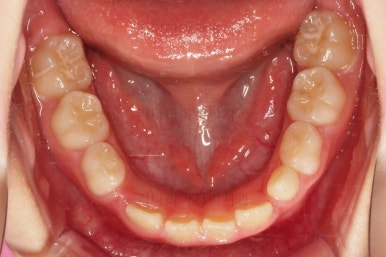

초진 시 입안의 모습입니다.

아래쪽 치열이 전반적으로 윗니보다 앞쪽에 위치한 전형적인 앵글씨 3급 부정교합인데요.

어금니에서부터 앞니까지 아랫니가 윗니보다 앞쪽에 위치하네요.

특히 앞니는 아랫니가 윗니보다 나와있는 "반대교합" 상태였고요.

또한 위아래로 겹침이 없고 떠있는 "개방교합" 상태였어요.

즉, 앵글씨 3급 부정교합 - 반대교합 - 개방교합 등 굉장히 복합적인 교합의 문제를 가진 환자였습니다.